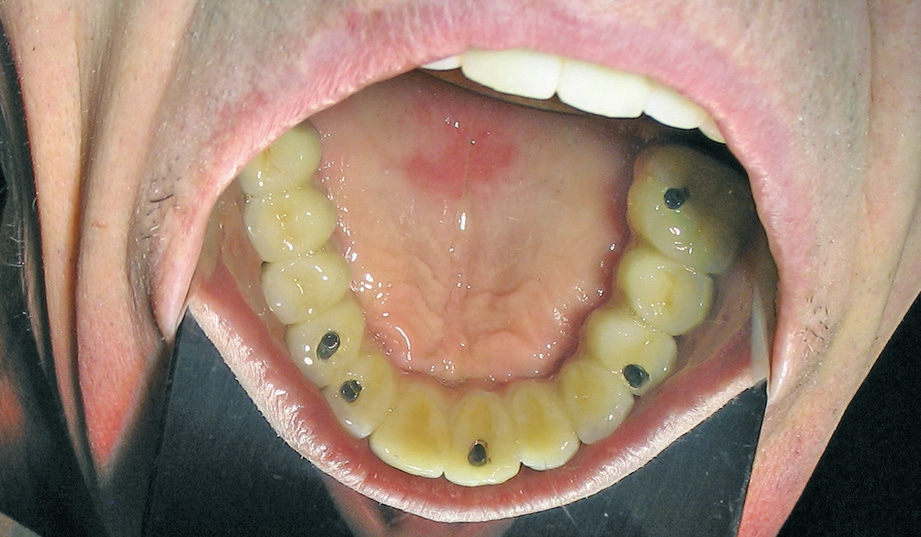

Für die Suprakonstruktionen wurde das Sekundärgerüst auf Abutment-Niveau gefräst. Der Patient bekam im Oberkiefer ein System mit interner Sechskantverbindung (Abb. 9-16). Die Patientin im Unterkiefer bekam ein System desselben Herstellers mit konischer Abutmentverbindung (Abb. 1-8). Davon ist ein Implantat noch in der Einheilphase verloren gegangen. Der betroffene Kiefer konnte trotzdem mit fünf Implantaten versorgt werden. Vom Prinzip „all-on-4“ wurde bewusst Abstand genommen. Ebenso wurde auch auf geneigt gesetzte Implantate verzichtet. Die Implantate, die abgewinkelte Abutments bekamen, wurden nach den prothetisch und anatomisch günstigsten Knochenverhältnissen gesetzt.